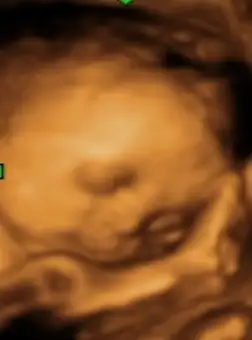

Kolay gelsin canım ne renk yaptınız?Kizlar iyi pazarlar herkeze bugun bebisimin odasi boyaniyor cok mutlu ve hala gribim :)

Kızlar iyi pazarlar herkese.. yarin kontrolumuz var.. acaba Nst'ye sokar mi bizi? Aranizda Nst'ye giren var mi?

Ben persembe gircem ilk defa 36. haftada..Kızlar iyi pazarlar herkese.. yarin kontrolumuz var.. acaba Nst'ye sokar mi bizi? Aranizda Nst'ye giren var mi?

Benimde kasikta sancı değil de ağrım var.. uzanirken, yataktan kalkarken falan bayagi canimi yakıyor.tethyss ben girdim geçenlerde gece kasık sancım olmuştu devlete gittim direk tahlil nst istedler.25dk kadar bi süre göbeğine cihaz bagliyorlar sen bu süre boyunca hareket etmeden uzaniyorsun. yanında monitör var orda bebeğin kalp atışı ve sancı aralığının rakamlari yazıyo ekranda.bebeğin kalp atışının sesini de duruyorsun zaten